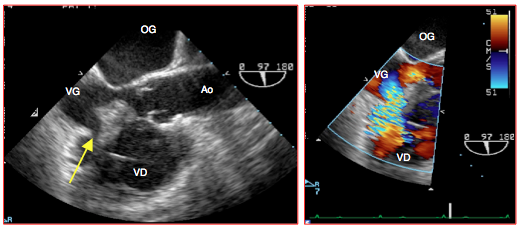

Figure 27.39 : Images ETO d'une cardiomyopathie hypertrophique sévère. A: vue 2-cavités transgastrique 90°. B: vue 4-cavités mi-œsophage qui met en évidence l'épaississement massif du septum interventriculaire.